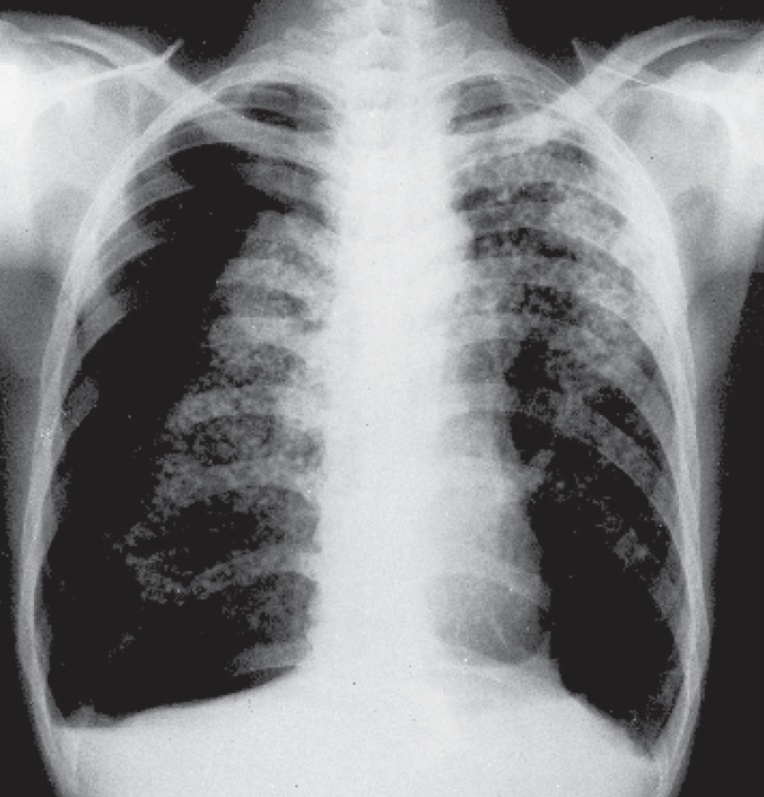

Dyspnea

N. K. Burki, MD, PhD

The survival of a patient with acute dyspnea may depend on your ability to identify and promptly treat the underlying cause.